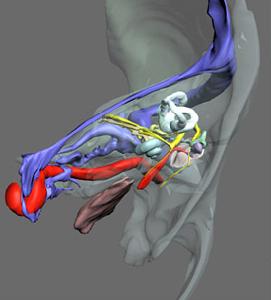

顳骨骨折(二)橫行骨折:主要由於枕部受到暴力所致。骨折線與岩骨長軸垂直,由顱底後窩橫過岩錐到顱中窩,多從枕骨大孔或頸靜脈窩,橫過內耳道和迷路到顱中窩的破裂孔或棘孔區。內耳損傷重,耳蝸及半規管內常有出血,迷路受損時有較重的眩暈、噁心、嘔吐,檢查可有傾倒及自發性眼球震顫,可持續數周,待對側代償後症狀消失。前庭功能檢查,患側功能喪失,聽力呈感音性耳聾。傷及中耳者較少,偶有迷路損傷同時中耳內壁也被震裂,導致蝸窗膜破裂,鼓室積血,約有半數並發麵癱,且為永久性癱瘓。

(三)岩尖骨折:很少見,可損傷及Ⅱ、Ⅲ、Ⅳ、Ⅴ、Ⅵ等顱神經,發生弱視,上瞼下垂,瞼裂變小,瞳孔擴大、復視、斜視,眼球運動受限等眼部症狀,或有三叉神經痛症狀,如損傷頸內動脈可發生大出血,多來不及搶救而死亡。